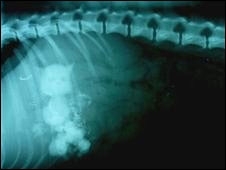

Snowy, uma West Highland terrier branca, estava vomitando tudo o que comia e foi submetida a um raio-X no veterinário na cidade de Huntingdon.

“Ficamos muito surpresos que um cachorro tão pequeno conseguiu engolir brinquedos desse tamanho”, disse o veterinário, Nigel Belgrove.

Segundo ele, a gata “mãe”, o brinquedo maior, tinha cerca de 5 cm, enquanto os gatos menores mediam 2,5 cm cada.

Segundo ele, a cadela teve sorte que os brinquedos, feitos de cerâmica, passaram pelo seu esôfago.

“Snowy tem apenas um ano de idade e pesa 5 quilos”, disse Belgrove.